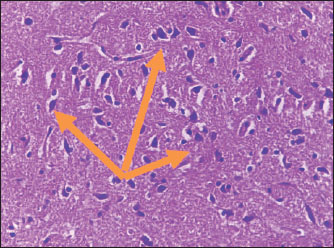

Brain of control group appeared normal structure of tissue with manifestation of Purkenji cells (Fig. 1), whereas sodium benzoate administration at low dose (200 mg/kg) occurred several histological lesions as hypertrophy of neurons (Fig. 2), pair nuclei arranged encompassed with clear space (Fig. 3), bleeding with degeneration of nerve cells (Figs. 4 and 5), respectively. In addition, lesions such as vacuolation, congestion, and accumulation of inflammatory cells were also evident (Figs. 6 and 7). However, severe histopathological lesions were observed following high-dose of sodium benzoate exposure, such as degeneration of neurons stained in dark blue (Fig. 8), prominent vascular duct with inflammation (Fig. 9), vacuolation, edema, and clear congestion as seen in Figures 1012, respectively.

Fig. 1. Points to the brain of control group: normal structure and manifestation of purkinje cells (H&E) (100 ×).

Fig. 2. Points to the brain of sodium benzoate group (200 mg/kg): hypertrophy of neurons (H&E) (100×).

Fig. 3. Points to the brain of sodium benzoate group (200 mg/kg): pair of nuclei ranking enclitic by clear area (H&E) (100×).

The histopathological lesions observed in the brain can be associated with two doses of sodium benzoate that cause defects in brain architecture. This agrees with the findings of Al-Ameen et al. (2022), who pointed to brain damage in the cortex, such as vacuolation, satellitosis, edema, and focal gliosis. The same study also described mild to severe changes according to the sodium benzoate ingestion dose. Similarly, a previous study by Mohammed and Al-Gnami (2022) referred to the passive histological effects of sodium benzoate in many tissues, causing vacuolation, degeneration, and infiltration of inflammatory cells. Furthermore, histopathological lesions may be due to DNA damage of neurons by sodium benzoate exposure. This is similar to the findings of Mohiuddin et al. (2022), who showed DNA fragments of rats treated with a high dose (120 mg/kg) of sodium benzoate.